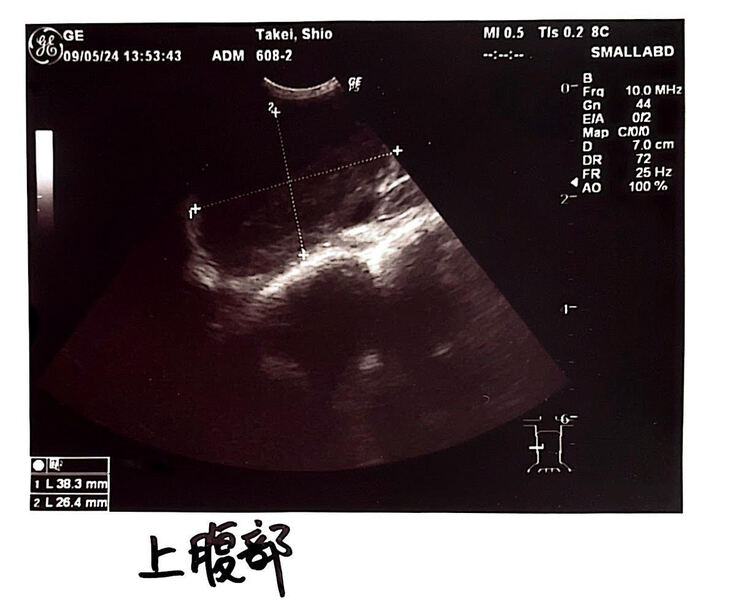

9月5日

検査の結果猫コロナウイルスの数値が

異常に高いとのことでした。

また発熱、食欲不振、体重減少も続いており

腹部エコーで腫瘍が見つかったため

FIPの可能性がとても高い

との診断となりました。

腹部エコーの写真です。

腹部には3×4㎜の腫瘍が見つかりました。

病院から掲載許可を得ております

↓